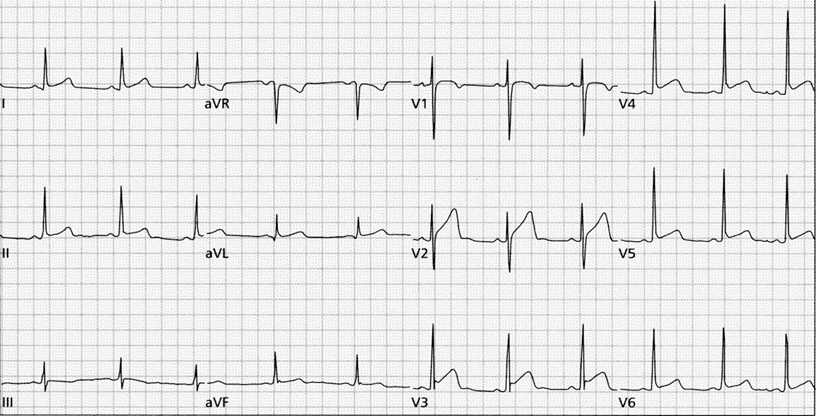

26-letnia kobieta została przyprowadzona do SOR przez swojego podenerwowanego chłopaka. Chłopak informuje lekarza o tym, że byli na dyskotece i nagle jego dziewczyna zaczęła się dziwnie czuć, kręciło się jej w głowie i powiedziała, że jej serce kołacze. Nie zgłaszała bólu za mostkiem ani duszności. Nigdy wcześniej tak się nie czuła. Parametry życiowe pacjentki były następujące: temperatura 36,5°C, RR 130/86, tętno 180/min, częstość oddechów 13/min. W badaniu fizykalnym nie wykazano żadnych odchyleń od fizjologicznej normy. W wykonanym badaniu EKG uzyskano zapis widoczny poniżej. Jaka jest pierwsza linia leczenia w przypadku tej pacjentki?

W poniższym zapisie EKG obserwujesz: (Przesuw taśmy 25 mm/s, cecha 10 mm=1 mV)

Mężczyzna nadużywający alkoholu, nieprzytomny podczas robienia EKG. W poniższym zapisie EKG obserwujesz: (Przesuw taśmy 25 mm/s, cecha 10 mm=1 mV)

Mężczyzna lat 68 zgłasza bolesność za mostkiem oraz uczucie zamroczenia. W poniższym zapisie EKG obserwujesz: (Przesuw taśmy 25 mm/s, cecha 10 mm=1 mV)

Pacjent po utracie przytomności. Ciśnienie tętnicze krwi 70/40 mmHg. W poniższym zapisie EKG obserwujesz: (Przesuw taśmy 25 mm/s, cecha 10 mm=1 mV):

Pacjent z zaburzeniami świadomości. W poniższym zapisie EKG obserwujesz: (Przesuw taśmy 25 mm/s, cecha 10 mm=1 mV)